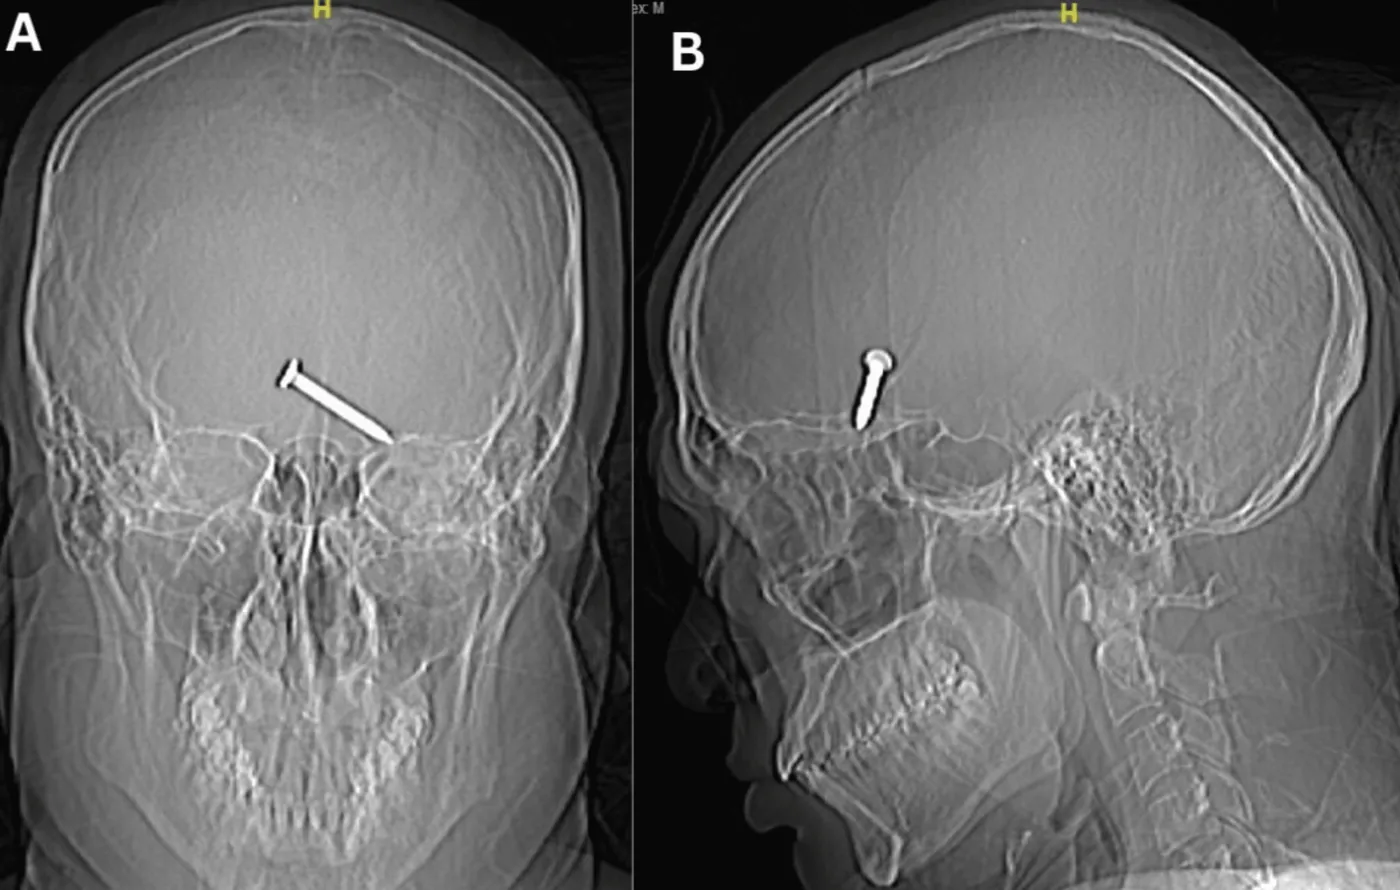

30-letni mężczyzna z poważną raną oka trafił do szpitala, prosto z budowy, gdzie pracował. Lekarze prześwietlili jego głowę. Nie mogli uwierzyć, co widzą na zdjęciach – gwóźdź tkwiący w płacie czołowym mózgu.

30-letni mężczyzna przypadkowo strzelił z gwoździarki w lewe oko w swoim miejscu pracy na budowie, podczas obsługi nieprawidłowo działającego sprzętu, wskutek czego doznał perforującego uszkodzenia lewego oka przez ciało obce, którego dostało się wewnątrz czaszki – czytamy w artykule w magazynie „Cureus”. Przypadkowo wystrzelony gwóźdź utkwił w płacie czołowym mózgu – sprecyzowali lekarze.

gwozdz-1-1-38057523.png

Gwóźdź w mózgu, źródło: „Cureus”

Mężczyzna miał również poważną ranę oka i popękaną kość sklepienia oczodołu. Szczęśliwie, jak pokazały zdjęcia rentgenowskie i tomografia komputerowa czaszki, gwóźdź o milimetry minął gałkę oczną i nie naruszył ważnych naczyń krwionośnych ani kluczowych nerwów, ale z uwagi na poważne uszkodzenie mózgu lekarze nie byli pewni, czy mężczyzna w ogóle przeżyje.